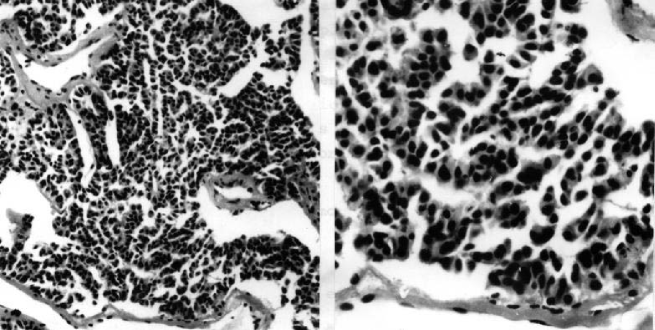

The introduction of the parameters was motivated by the fact that tumor cell shape (see Figures 6 and 7) represents a visual manifestation of an underlying balance of forces and chemical reactions [32]. Specifically, the parameters represent the following quantities:

The ability to estimate the growth pattern of an individual tumor cell type on the basis of morphological measurements should have general applicability in cellular investigations, cell–growth kinetics, cell transformation and morphogenesis [34].

The proposed model (20)–(23) describes chaotic behavior relevant to the invasion of cancer cells (see Figures 5 and 6). As devices for controlling metastasis/chaos we suggest the following processes: Cellular retraining of cancer stem cells and/or activation of positive function of cyclin-dependent kinase inhibitor p27 and/or decreased expression of SATB1, which is correlated with aggressive tumor phenotype in breast cancer and shorter patient survival time [27, 29, 30, 31].